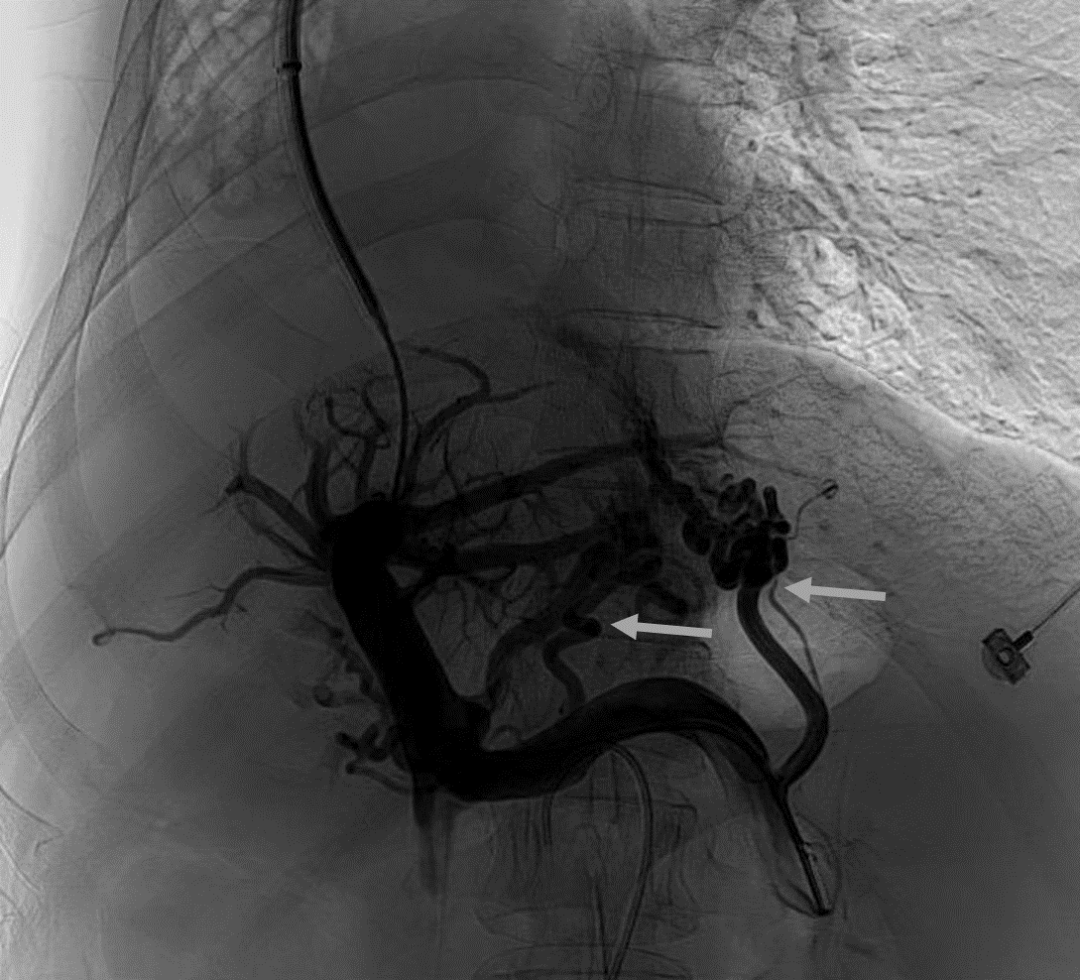

韓國(guó)宏教授介紹,TIPS手術(shù)是通過(guò)在肝靜脈與門(mén)靜脈之間的肝實(shí)質(zhì)內(nèi)建立分流通道,通過(guò)降低門(mén)靜脈壓力來(lái)預(yù)防和治療因門(mén)靜脈高壓引起的食管胃底曲張靜脈破裂出血或頑固性腹水。該手術(shù)不用開(kāi)刀、創(chuàng)傷小、操作過(guò)程復(fù)雜、技術(shù)難度大、安全風(fēng)險(xiǎn)高,是目前外周血管介入中難度最大的手術(shù)之一。再加上人群中右位心發(fā)病率極低(約萬(wàn)分之一),經(jīng)查閱文獻(xiàn),在國(guó)內(nèi)外尚未有類(lèi)似病例報(bào)道,無(wú)經(jīng)驗(yàn)參考。在右位心基礎(chǔ)上行TIPS術(shù),無(wú)疑是難上加難。我們反復(fù)研究患者肝臟及心血管的特殊情況,詳細(xì)討論了手術(shù)方案,決定放棄常規(guī)的肝靜脈穿刺,另辟蹊徑,選擇高難度高風(fēng)險(xiǎn)的肝后段下腔靜脈穿刺門(mén)靜脈左支,憑借多年的經(jīng)驗(yàn)和嫻熟的技術(shù)最終成功的在下腔靜脈與門(mén)靜脈之間放置了TIPS專(zhuān)用支架,術(shù)后門(mén)靜脈壓力梯度從術(shù)前的19mmHg降至3mmHg,曲張靜脈消失,解決了困擾曹女士多年上消化道出血的困擾?;颊咝g(shù)后第二天即可正常下床活動(dòng)。